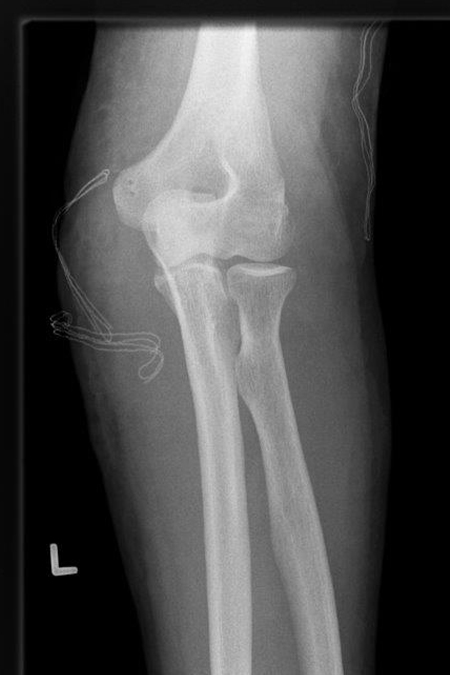

Die Operation dieser komplizierten Verletzungen zielt darauf ab die verletzten Bandansätze (ulnares und radiales Seitenband, beugeseitige Kapsel) wie auch die knöchernen Verletzungen (Speichenköpfchenbruch – oft zertrümmert, proc. Corornoideus) stabil wieder her zu stellen. Ziel ist es das Ellenbogengelenk frühzeitig stabil zu bewegen, um eine Einsteifung zu verhindern.

Rechtshändiger Fotograf mit hoch instabiler Ellenbogenluxationsverletzung links. Operative Stabilisation mit Rekonstruktion der Bandstrukturen des Ellenbogengelenkes außen und innenseitig unter Einsatz einer Augmentationstechnik (Internal Bracing).

Reponiertes Gelenk nach operativer Stabilisation

63-jähriger Mann mit einer vollständiger Ellenbogenluxationsverletzung und ausgeprägter Instabilität nach Einrichtung des Gelenkes. Im Rahmen der Operation wurde das Ellenbogengelenk auf der Außenseite zuerst mit einer Bandstabilisation und Augmentation (Fiber Tape) stabilisiert und anschließend auch ellenseitig eine Bandstabilisation durchgeführt. Gutes Ergebnis nach 8 Wochen.

Ellenbogengelenk zentriert nach Operation frontal

Ellenbogengelenk zentriert nach Operation seitlich